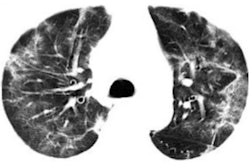

Intelligent Evaluation System of Chest CT uses algorithms to quantitatively analyze key imaging features from CT scans to detect and assess COVID-19, according to the vendor. The software grades the severity of pneumonia diseases using lesion morphology, range, and density. It can also quantify the cumulative pneumonia load of the disease, the company said.

The system can automatically detect the lesion area and perform its analysis in 2 to 3 seconds, Yitu Healthcare said. Shanghai Public Health Clinical Center shared its experience with using the software in an article posted on its official WeChat platform on February 4.